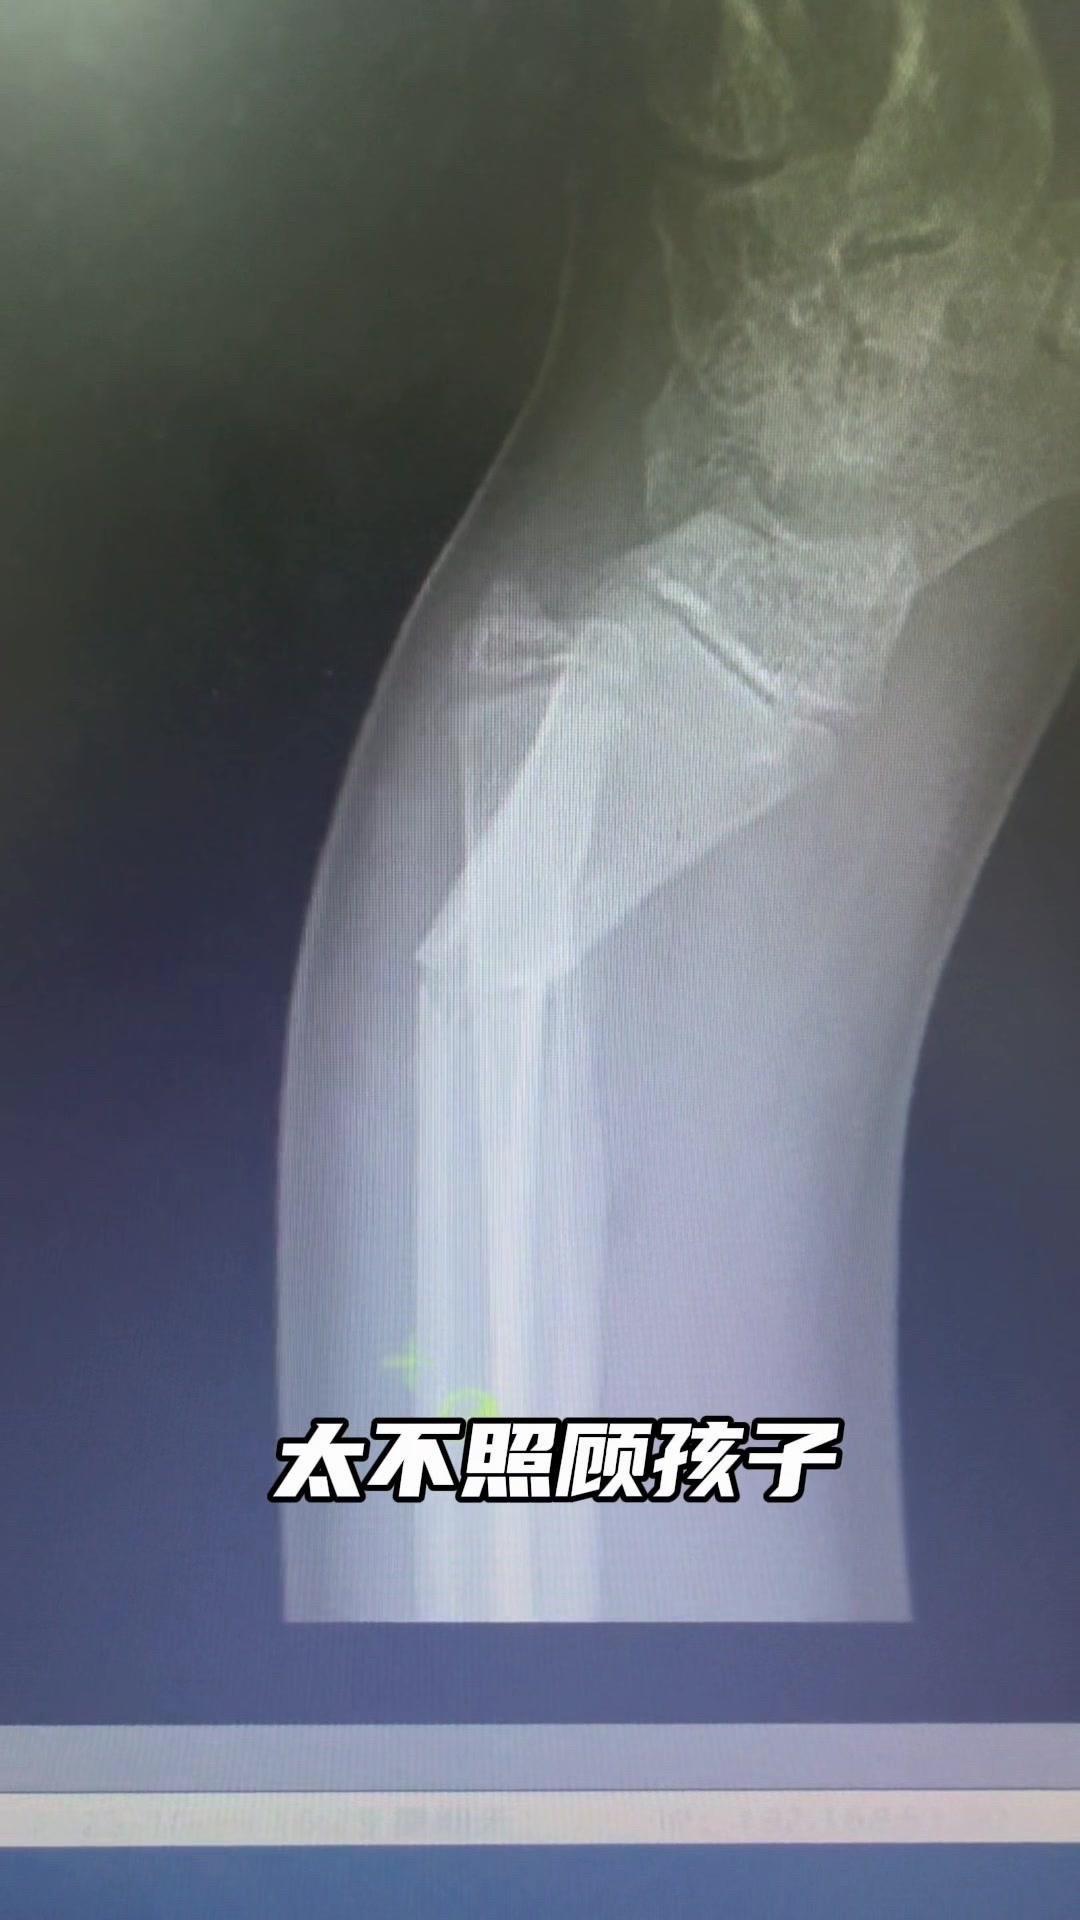

儿童骨折别拖延!💡上周接诊一个10岁女孩,摔了一跤后腕部疼痛还伴有畸形,家长觉得是小伤没在意,结果一周后孩子疼得更厉害,畸形也更明显了。来医院拍片一看,妥妥的骨折,而且才一周就开始出现模糊骨痂,掌区还有45度左右的成角畸形。家长这才意识到问题严重性,其实孩子受伤后出现疼痛、畸形,哪怕看起来不严重,也得及时检查,别让小问题拖成大麻烦。